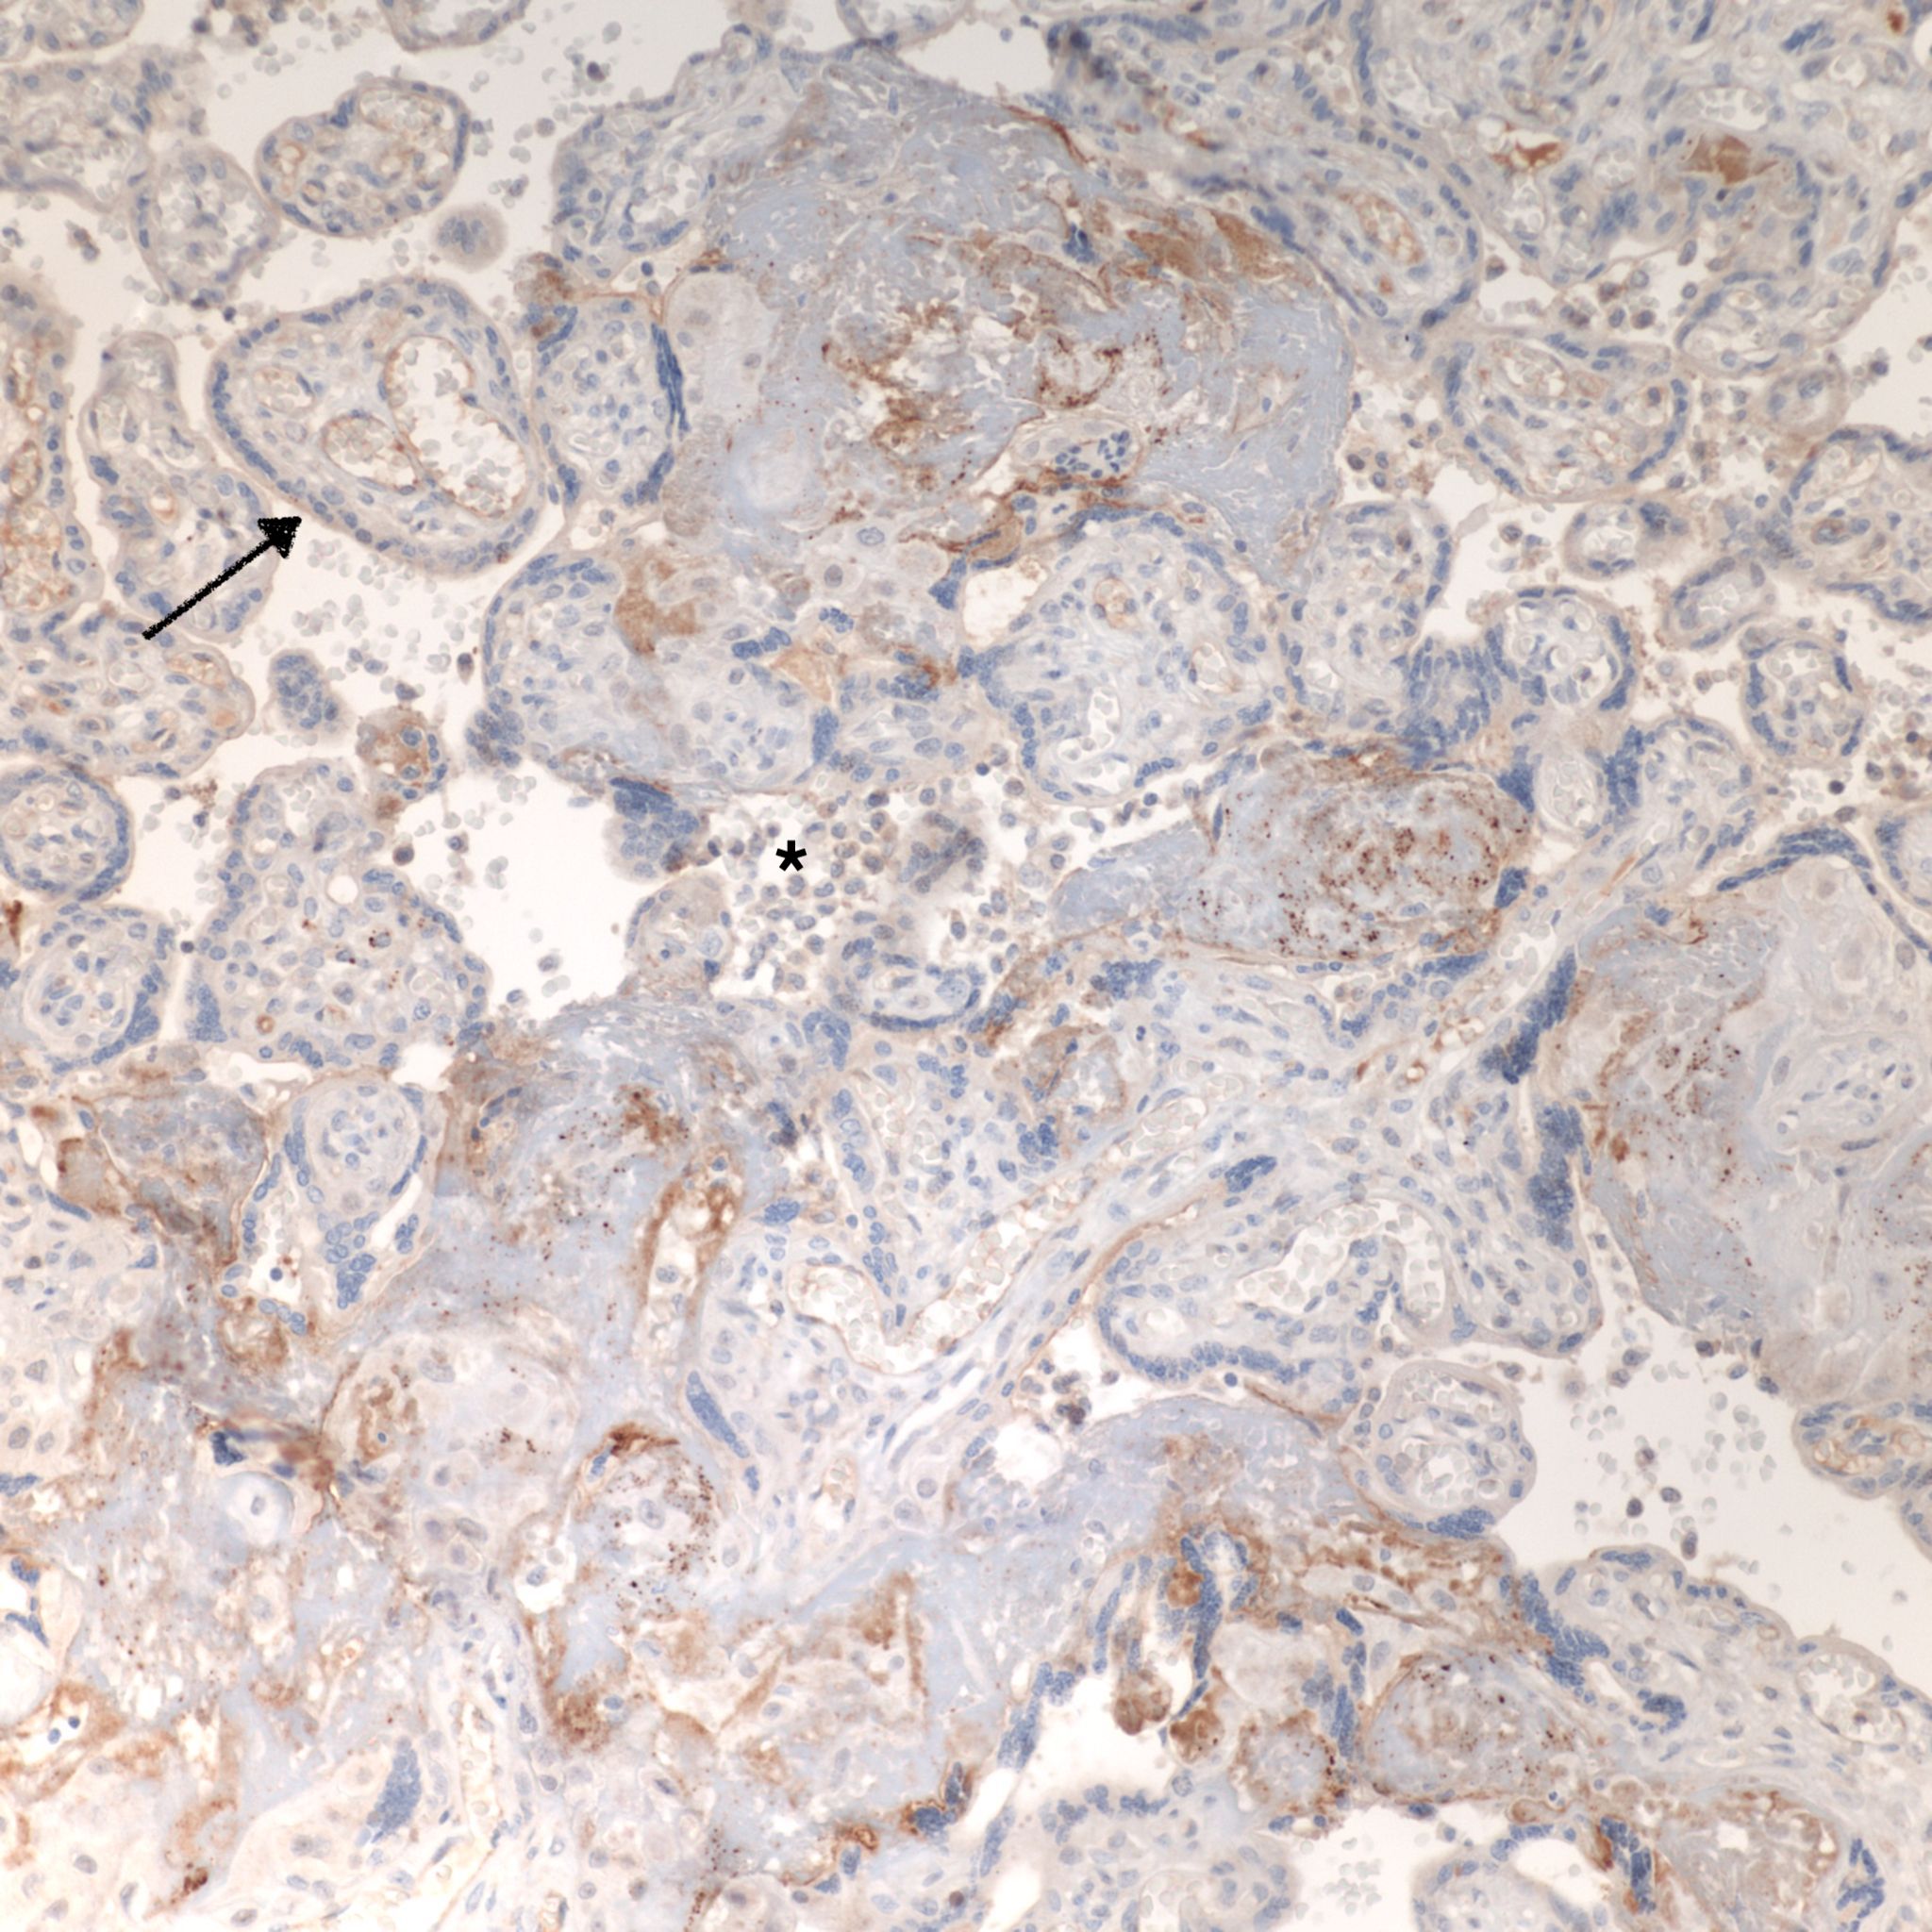

CD68 or alkaline phosphatase: to confirm that the intervillous cells are monocytes, but is not required for meeting the diagnostic criteria

C4d: to show evidence of complement fixation on the microvillous surface of the syncytiotrophoblast. While further study is needed, the subclassification of intervillous monocyte accumulations into those with and without complement fixation and the subclassification of villitis of unknown aetiology with intervillous monocytes into those with and without complement fixation may prove to be a useful distinction.

C4d: One study of CHIV compared 3 histologic groups of placentas demonstrating intervillous histiocytes: Few intervillous monocytes, massive intervillous monocytes, and intervillous monocytes associated with villitis of unknown aetiology18. Each group was further divided into subcategories based on the extent of c4d immunostaining of the microvillous surface of the syncytiotrophoblast. The outcome variables were fetal death or growth restriction. In the analysis, without a formal ROC study, it appeared that staining less than 25% of the villous surface was a natural cut off point from greater than 25%. As can be seen in the Table 1 of the raw data, that with rare exceptions, all the cases with less than 25% of c4d trophoblast staining, and often without any staining, were either associated with few intervillous monocytes, or with villitis. Fetal death or growth restriction was almost always associated with more than 25% of the villous surface stained with c4d. The lack of statistical significance in the comparisons is likely due to small sample size.

CHIV with prominent perivillous fibrinoid deposition

CHIV associated with Villitis of Uknown Etiology (VUE)

This pattern could be due to a primary cause of VUE with incidental chemotaxis of monocytes, two pathogenetically interrelated processes, or an incidental focus of VUE in a predominant CIIV disease. Currently, describing the extent of each process and its colocalization or lack of may prove useful until a better way to classify the co-existing lesions can be developed. One study has shown that there is a dichotomy between cases with c4d staining and those without c4d staining18.